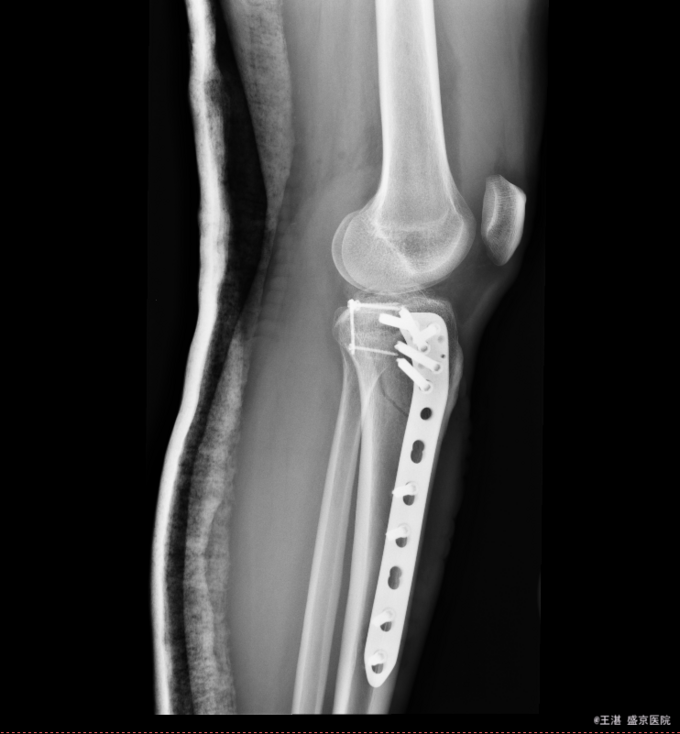

患者及家属自诉于2015年11月28日晚9点在沈阳市铁西区自己摔倒,摔倒后左下肢疼痛,活动受限,不能活动,急送至沈阳八院急诊,行DR提示:左胫骨近端粉碎性骨折。后送至我院急诊,行左膝关节CT后以“左胫骨近端粉碎性骨折”为主要诊断收入我科。患者轮椅入病房,无发热,无头晕头迷,无胸闷气短,无心慌心悸,无腹痛腹胀,受伤后排气正常,大小便未排。

专科查体:患者轮椅入病房。左小腿活动受限,压痛(+),叩击痛(+),双下肢皮肤感觉正常,足背动脉可扪及搏动,末梢血运良好,足趾活动灵活。 辅助检查:左膝关节CT:(我院,2015-11-29):左胫骨近端粉碎性骨折。

患者入院后完善相关检查,明确诊断,手术指征明确,于2015-12-2日于全麻下行左胫骨平台骨折切开复位内固定术,术后经抗炎、止疼等对症治疗后,患者恢复顺利,切口愈合良好,可出院。